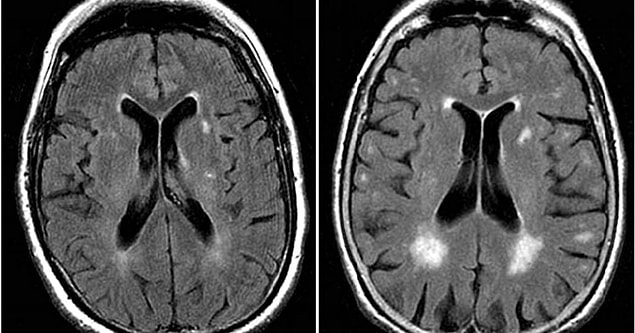

Demans aslında sanıldığı üzere tek bir hastalık değildir. Pek çok tipi bulunan bu hastalığın en sık gözlenen çeşidi olan Alzheimer demansı bütün demansların yaklaşık %60 ila %80’inden sorumludur. Hastalık kendini hafıza ve düşünme yeteneği, dikkat, karar alma, lisan ve konuşma merkezindeki bozulmalarla gösterebilir. Demans için şu anda çok az tesirli tedavi bulunuyor. Uzmanlar bunun kısmen durumun ekseriyetle semptomlar ortaya çıktıktan sonra teşhis edilmesinden kaynaklandığını, fakat altta yatan sorunun yıllar hatta on yıllar evvel başlamış olabileceğini söylüyor.

Bilim insanları, hastalara kesin bir teşhis konmadan yıllar evvel demansı tespit etmenin mümkün olabileceğini zira hastanın dokuz yıl öncesinden belirti gösterdiğini keşfettiler. Bu bulgular sayesinde artık risk altındaki şahıslar tespit edilebilir yahut yeni tedaviler için klinik deneylere uygun hastaları belirlenebilir.

Şimdiye kadar, semptomların başlangıcından evvel beyin işlevindeki değişiklikleri tespit etmenin mümkün olup olmadığı meçhuldü.